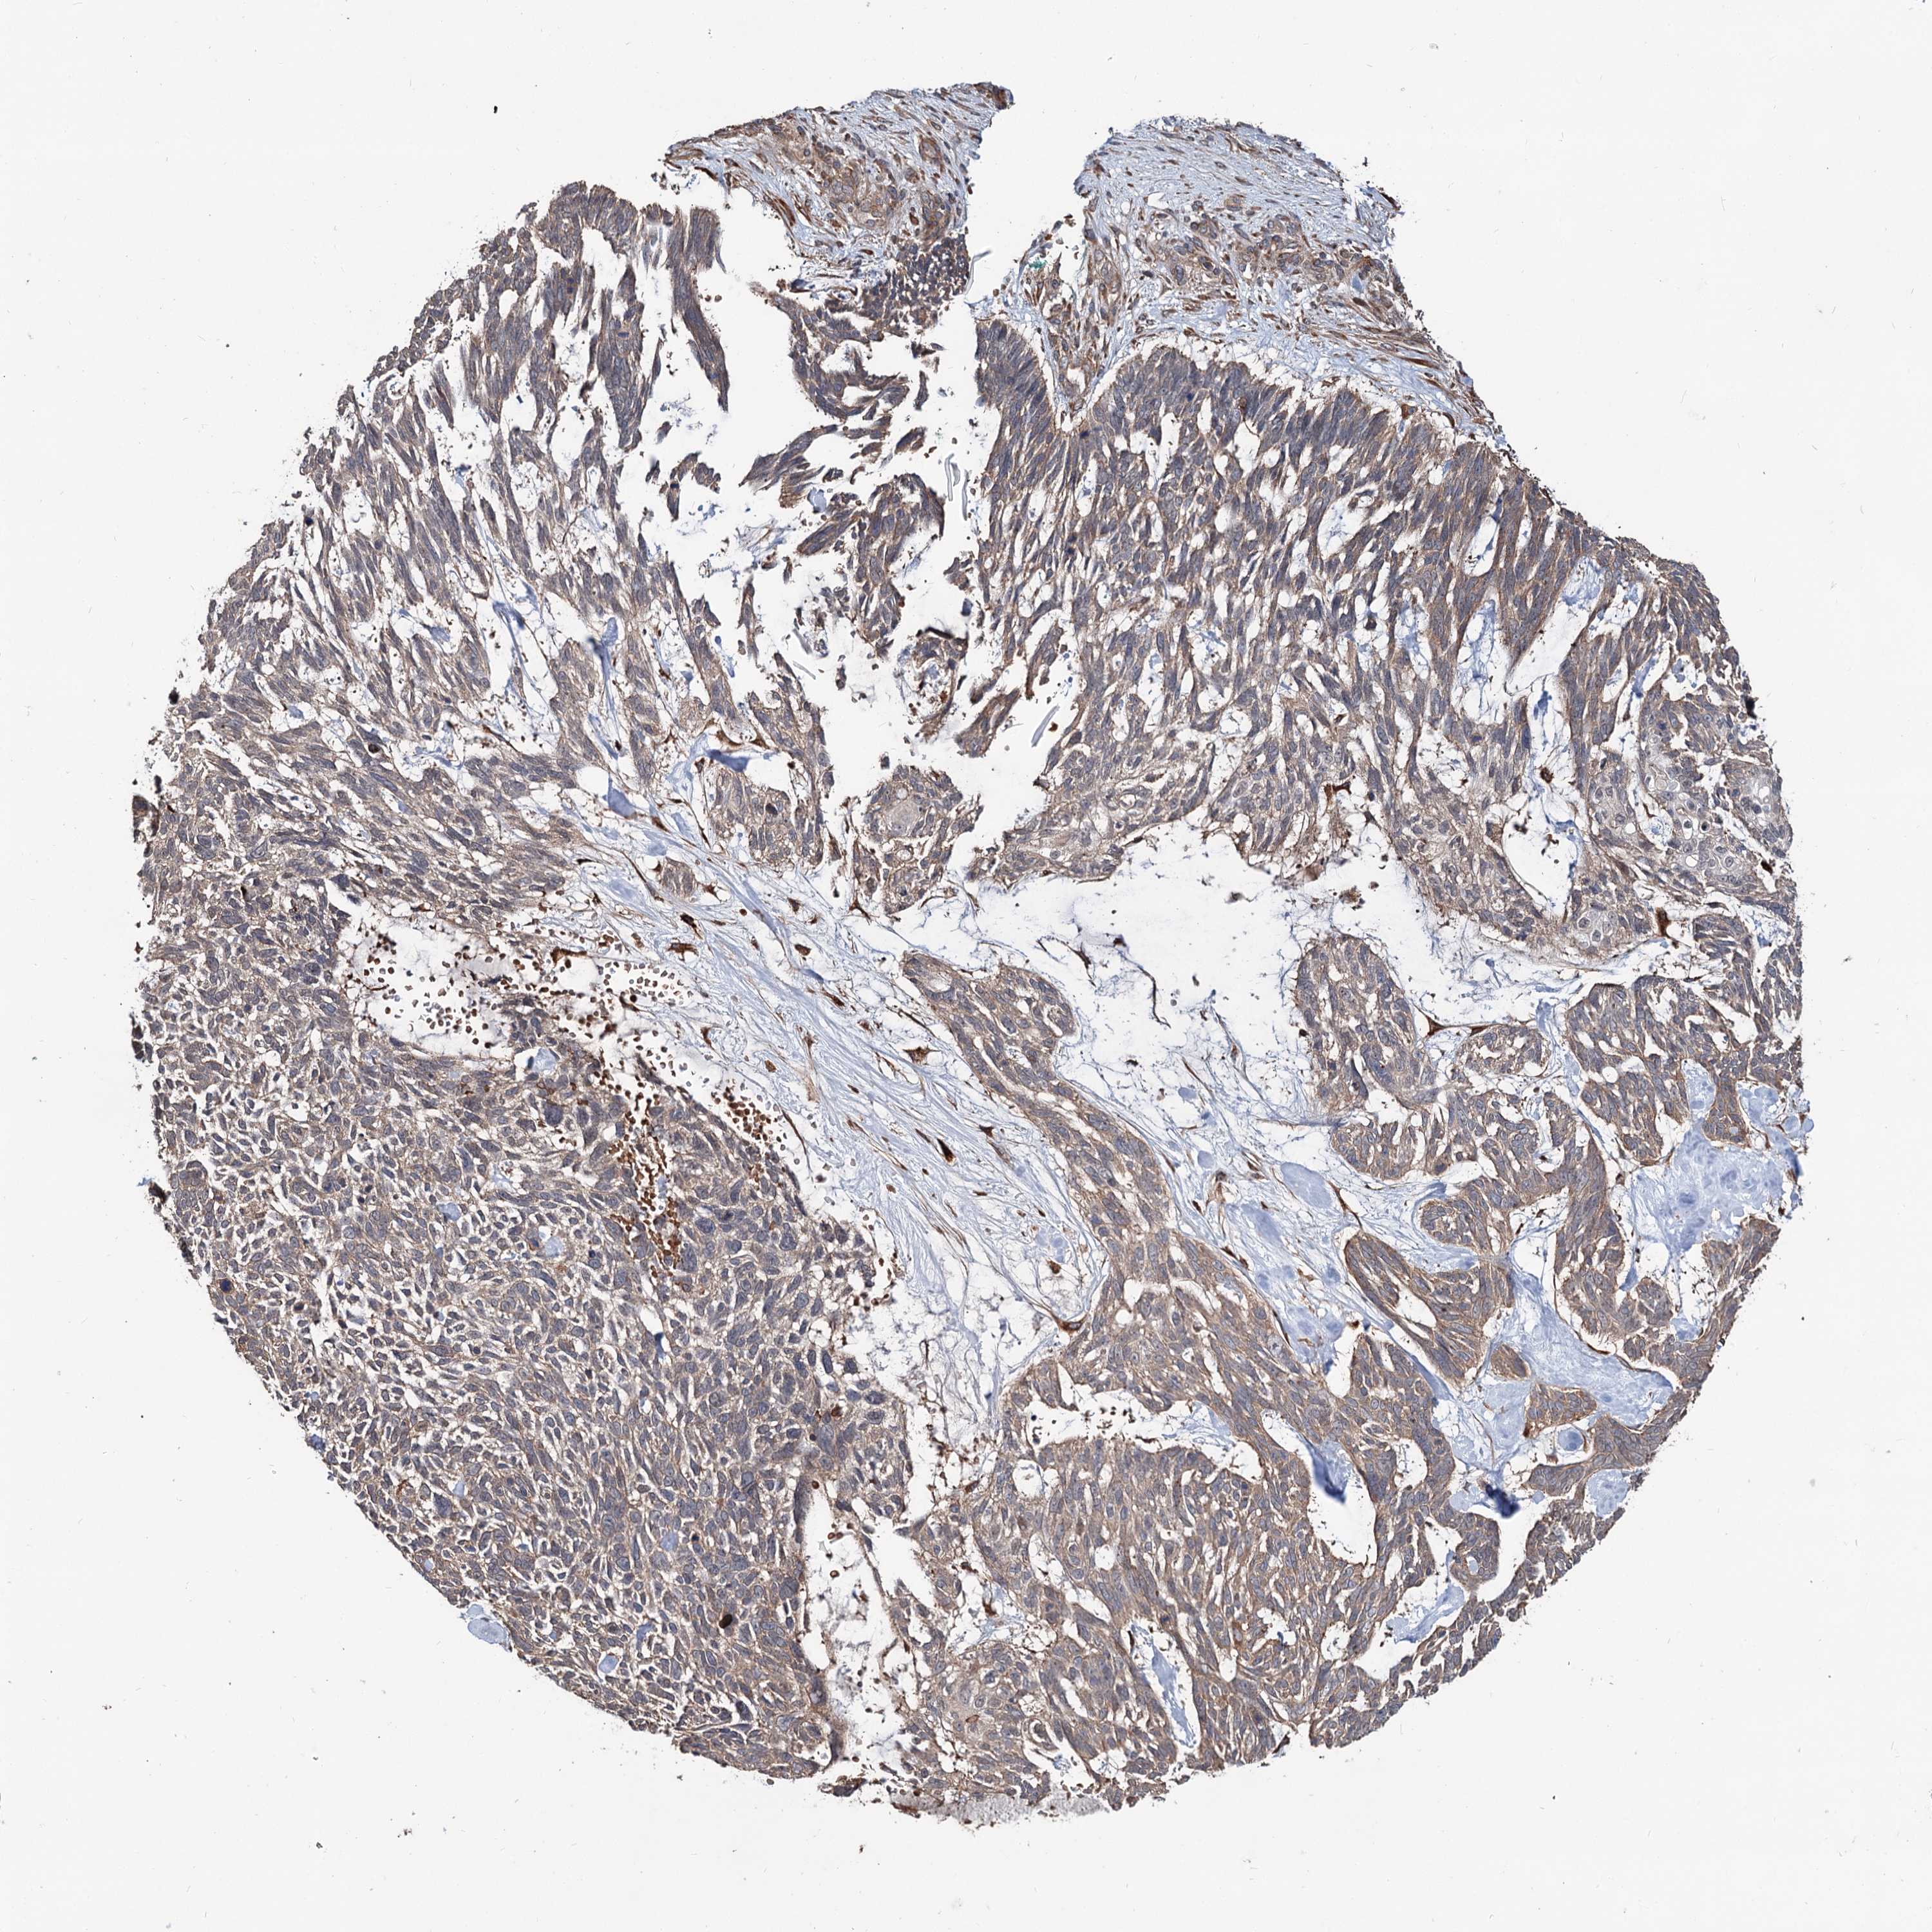

CANCER SKIN CANCER Show tissue menu

Basal cell and squamous cell cancer

SKIN CANCER - Protein expressioni

A mouse-over function shows sample information and annotation data. Click on an image to view it in a full screen mode. Samples can be filtered based on level of antibody staining by selecting one or several of the following categories: high, medium, low and not detected. The assay and annotation is described here.

Each image is clickable and will lead to virtual microscopy that enables deeper exploration of all samples and also displays staining intensity scores, fraction scores and subcellular localization as well as patient and tissue information for each sample.

Antibody HPA038856

Staining

High

Strong

Quantity

Location

Basal cell carcinoma

Squamous cell carcinoma, NOS

Squamous cell carcinoma, metastatic, NOS